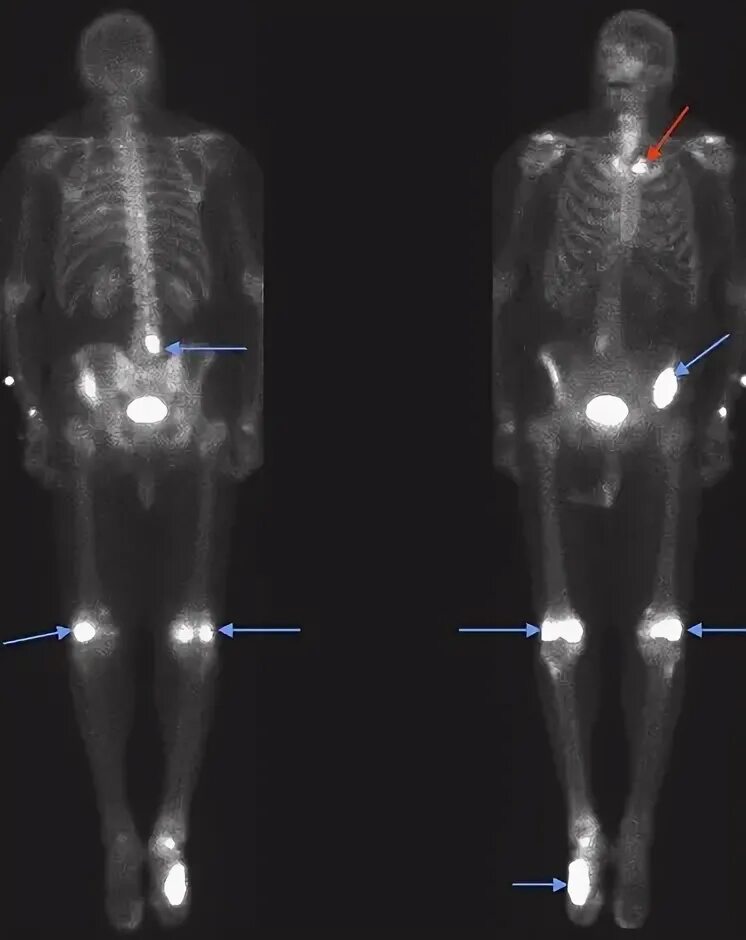

Метастазы костей мрт